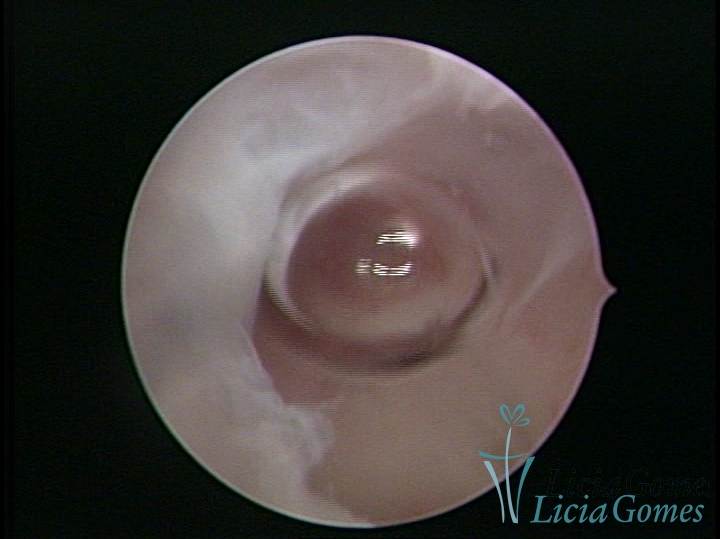

FIBROUS SYNECHIA

Uterine synechiae are scars (adherence) between the surface of the uterine walls, which may occur after the surgical procedure, uterine curettage, or after an inflammatory process in the uterine cavity (endometritis), which may lead to menstrual changes, infertility and obstetric complication such as abortion and premature birth.